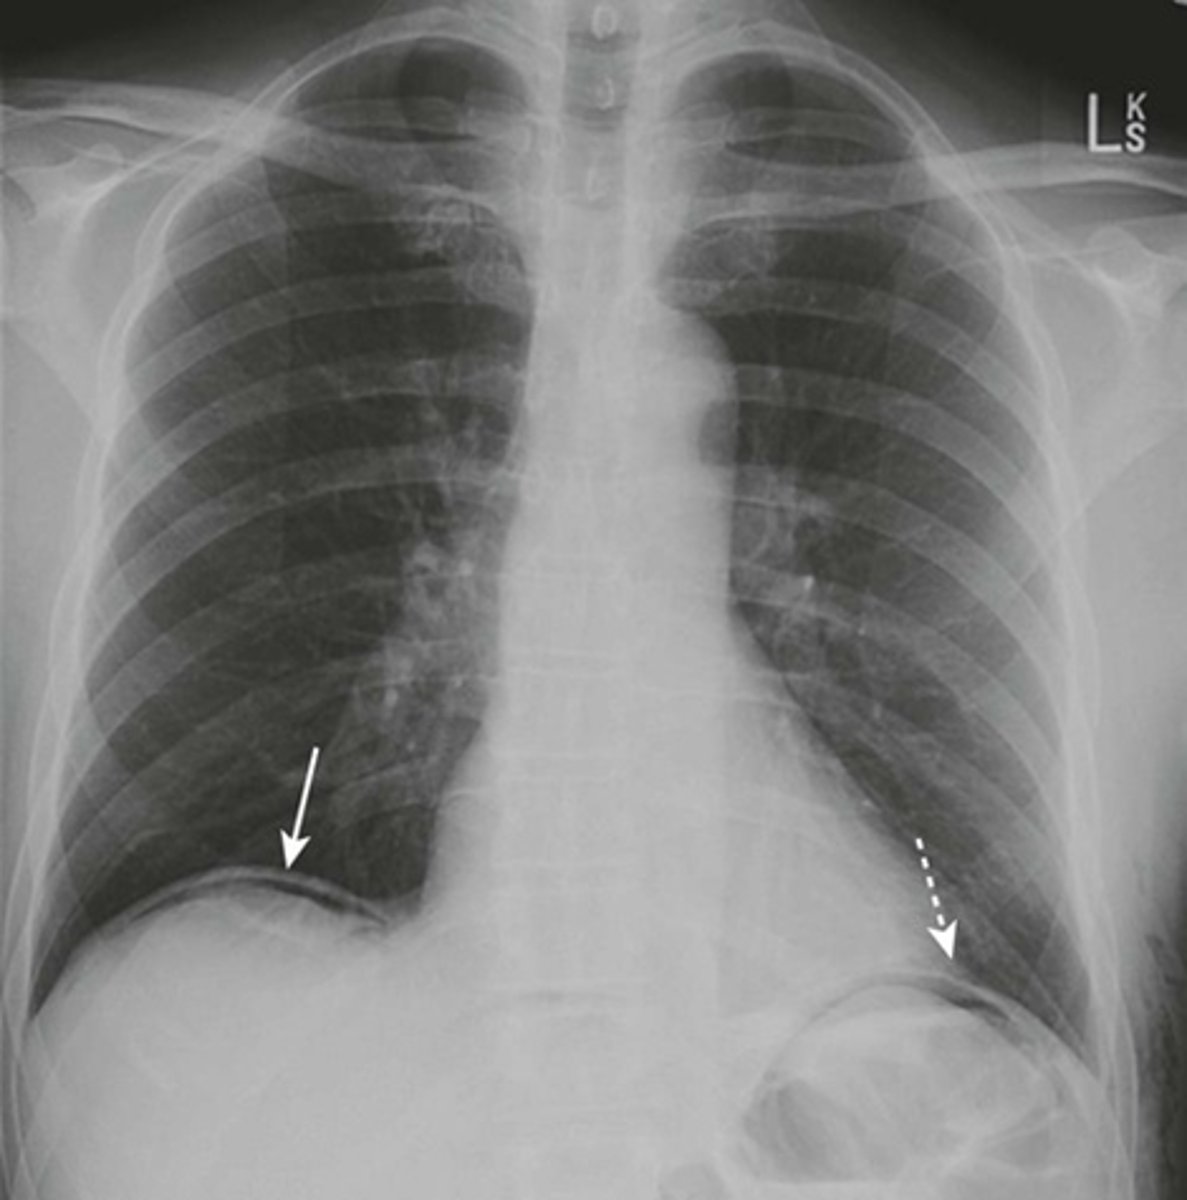

Esophageal diverticula.

(A)WHITE ARROW:

localized weakness in the posterior wall of the hypopharynx;

in the mid-esophagus from extrinsic disease such as tuberculosis that causes fibrosis, which pulls on the esophagus, forming a traction diverticulum (dotted white arrow)

DOTTED WHITE ARROW:

traction diverticulum. fibrosis pulling on the esophagus.

B: BLACK ARROW:

Epiphrenic diverticulum, just above the diaphgram in the distal esophagus.

(C). Only the traction diverticulum is a true diverticulum in that it has all layers of the esophagus involved; the Zenker and epiphrenic are false or pseudodiverticula because the mucosa and submucosa herniate through a defect in the muscular layer. The Zenker diverticulum is the only one of the three that typically produces symptoms.